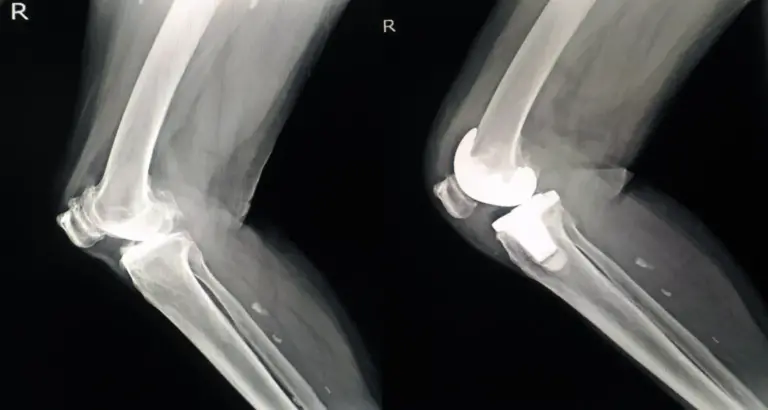

Explore the intricacies of a healthy knee joint through X-ray imaging, radiographic techniques, and advanced diagnostics in this insightful article.

Discover the difference between normal and abnormal knee joint X-ray. Learn what a normal knee X-ray looks like and identify abnormalities.